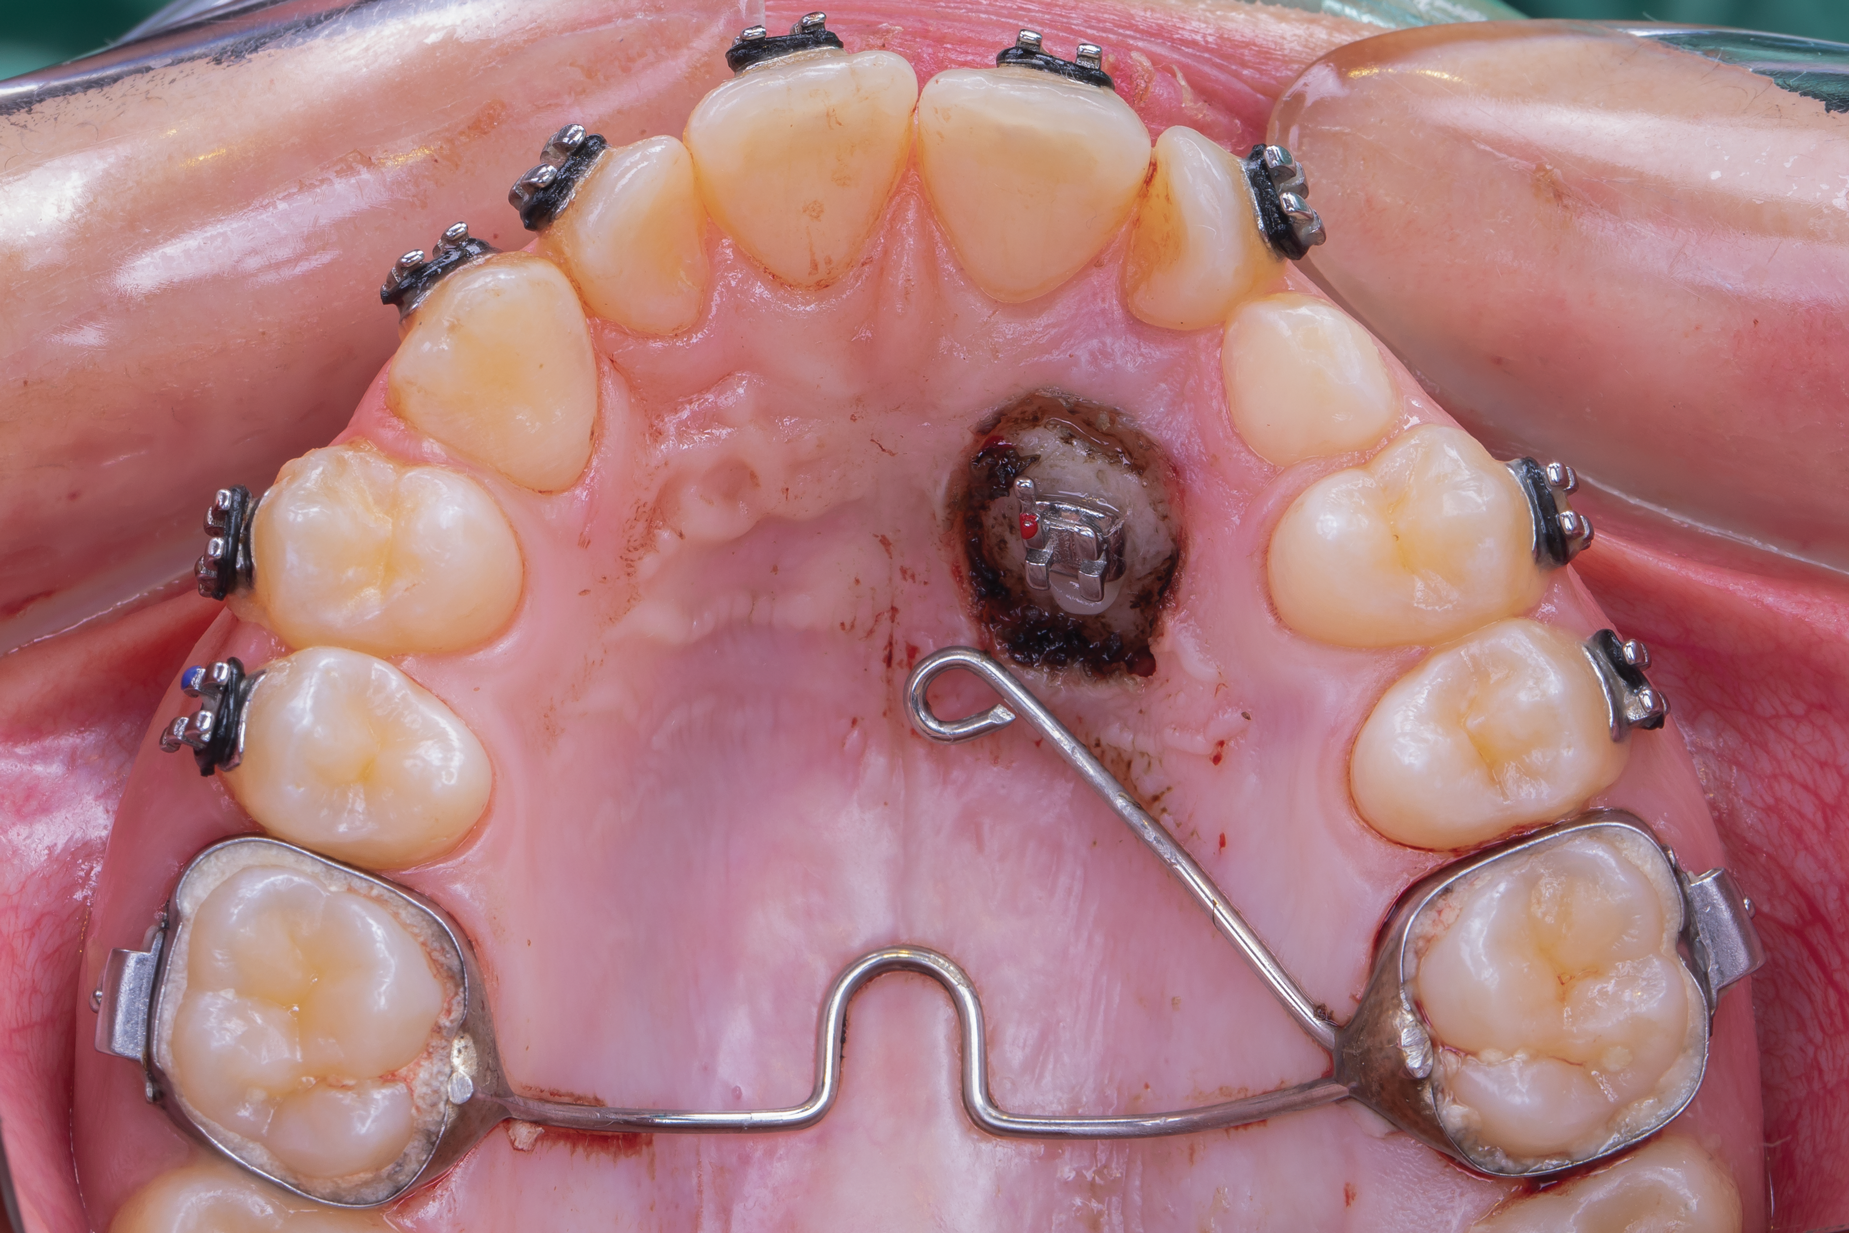

Fig 4. Swinging gate type of auxiliary used for direct traction of a palatal canine managed with open exposure.

Figure 4

Fig 5. Open exposure of a palatal impacted canine. A transpalatal bar was used as an anchorage source with an extension arm designed for direct traction.

Figure 5